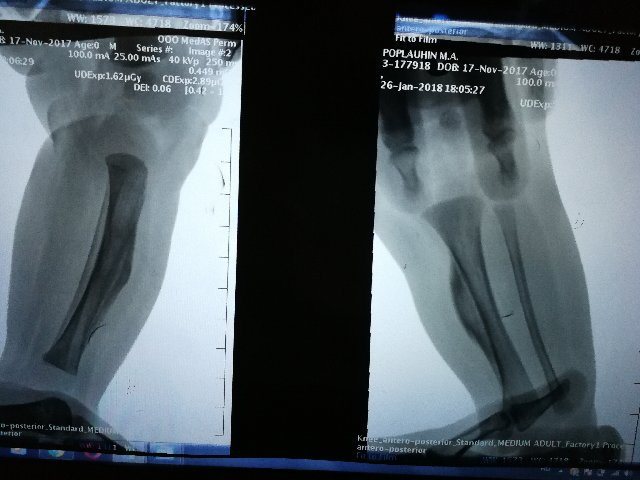

Гиперостоз на месте, искривление голени присутствует, но уменьшается. Ребенку не мешает. В тот раз не приложились снимки, прикладываю для истории снова.

Слева легкий вальгус. Сохраняется зажимание указательных пальцев, особенно слева, в играх на мелкую моторику.  Учу контролировать. Все равно предпочитает правую сторону.